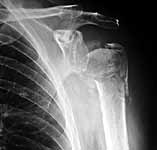

49 yo male RHD architect 3 mos s/p left prox humerus fx/dislocation in MCA presented today wanting know if he had any other treatment options at this time. He had initial PP, which was better reduced, but fell back into valgus impaction. He has 45 degrees FF, 40 degrees Abduction, 20 degrees ER of motion now w/ limited function.

It's hard to tell from the xrays exactly how thin the head fragment is but I wonder if you were able to get screws right up to the subchondral bone, backfilling the impacted area well with bone graft, and be a little more protective, if you wouldn't be able to get it to heal. I think that a hemiarthroplasty, while certainly a reasonable choice, burns another bridge. Tough case for sure.

Attached are pics of malunion w/ osteotomy and fixation w/ Norian in gap after improving valgus impaction.

Xrays look better. We will see if he improves as well.